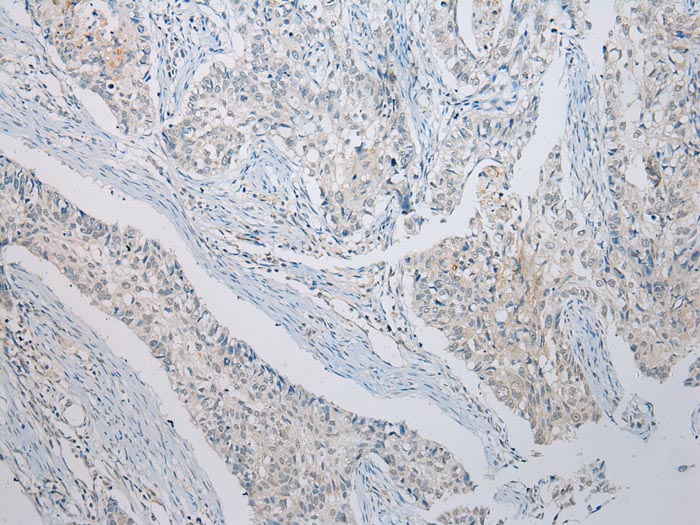

分类: 科研抗体货号: P43008别名:应用: WB,IHC反应种属: Human,Mouse,Rat